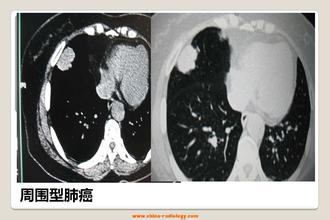

3)肺部肿瘤:分良性肿瘤(炎性假瘤、错构瘤)、恶性肿瘤(肺癌或肺继发转移癌)。大家担心的是肺癌,肺癌患者常常发生于长期吸烟、年龄40~50岁以上、有刺激性干咳或咳嗽咳痰、痰中带血、胸闷、胸痛、体重明显下降、乏力等不适症状,实验室检查血肿瘤标志物可以升高、痰或肿块穿刺活检、纤维支气管镜活检可找到癌细胞,影像学有特殊表现(如胸部CT提示肺部结节呈“分叶状”或有“毛刺征”,转移性肺癌其肿块边缘一般比较光滑,肺内易出现多个类似结节)。若明确诊断肺癌,则应及时到肿瘤专科行规范治疗,选择手术或放化疗或靶向治疗等治疗手段,而不应该道听途说病急乱投医,贻误病情。